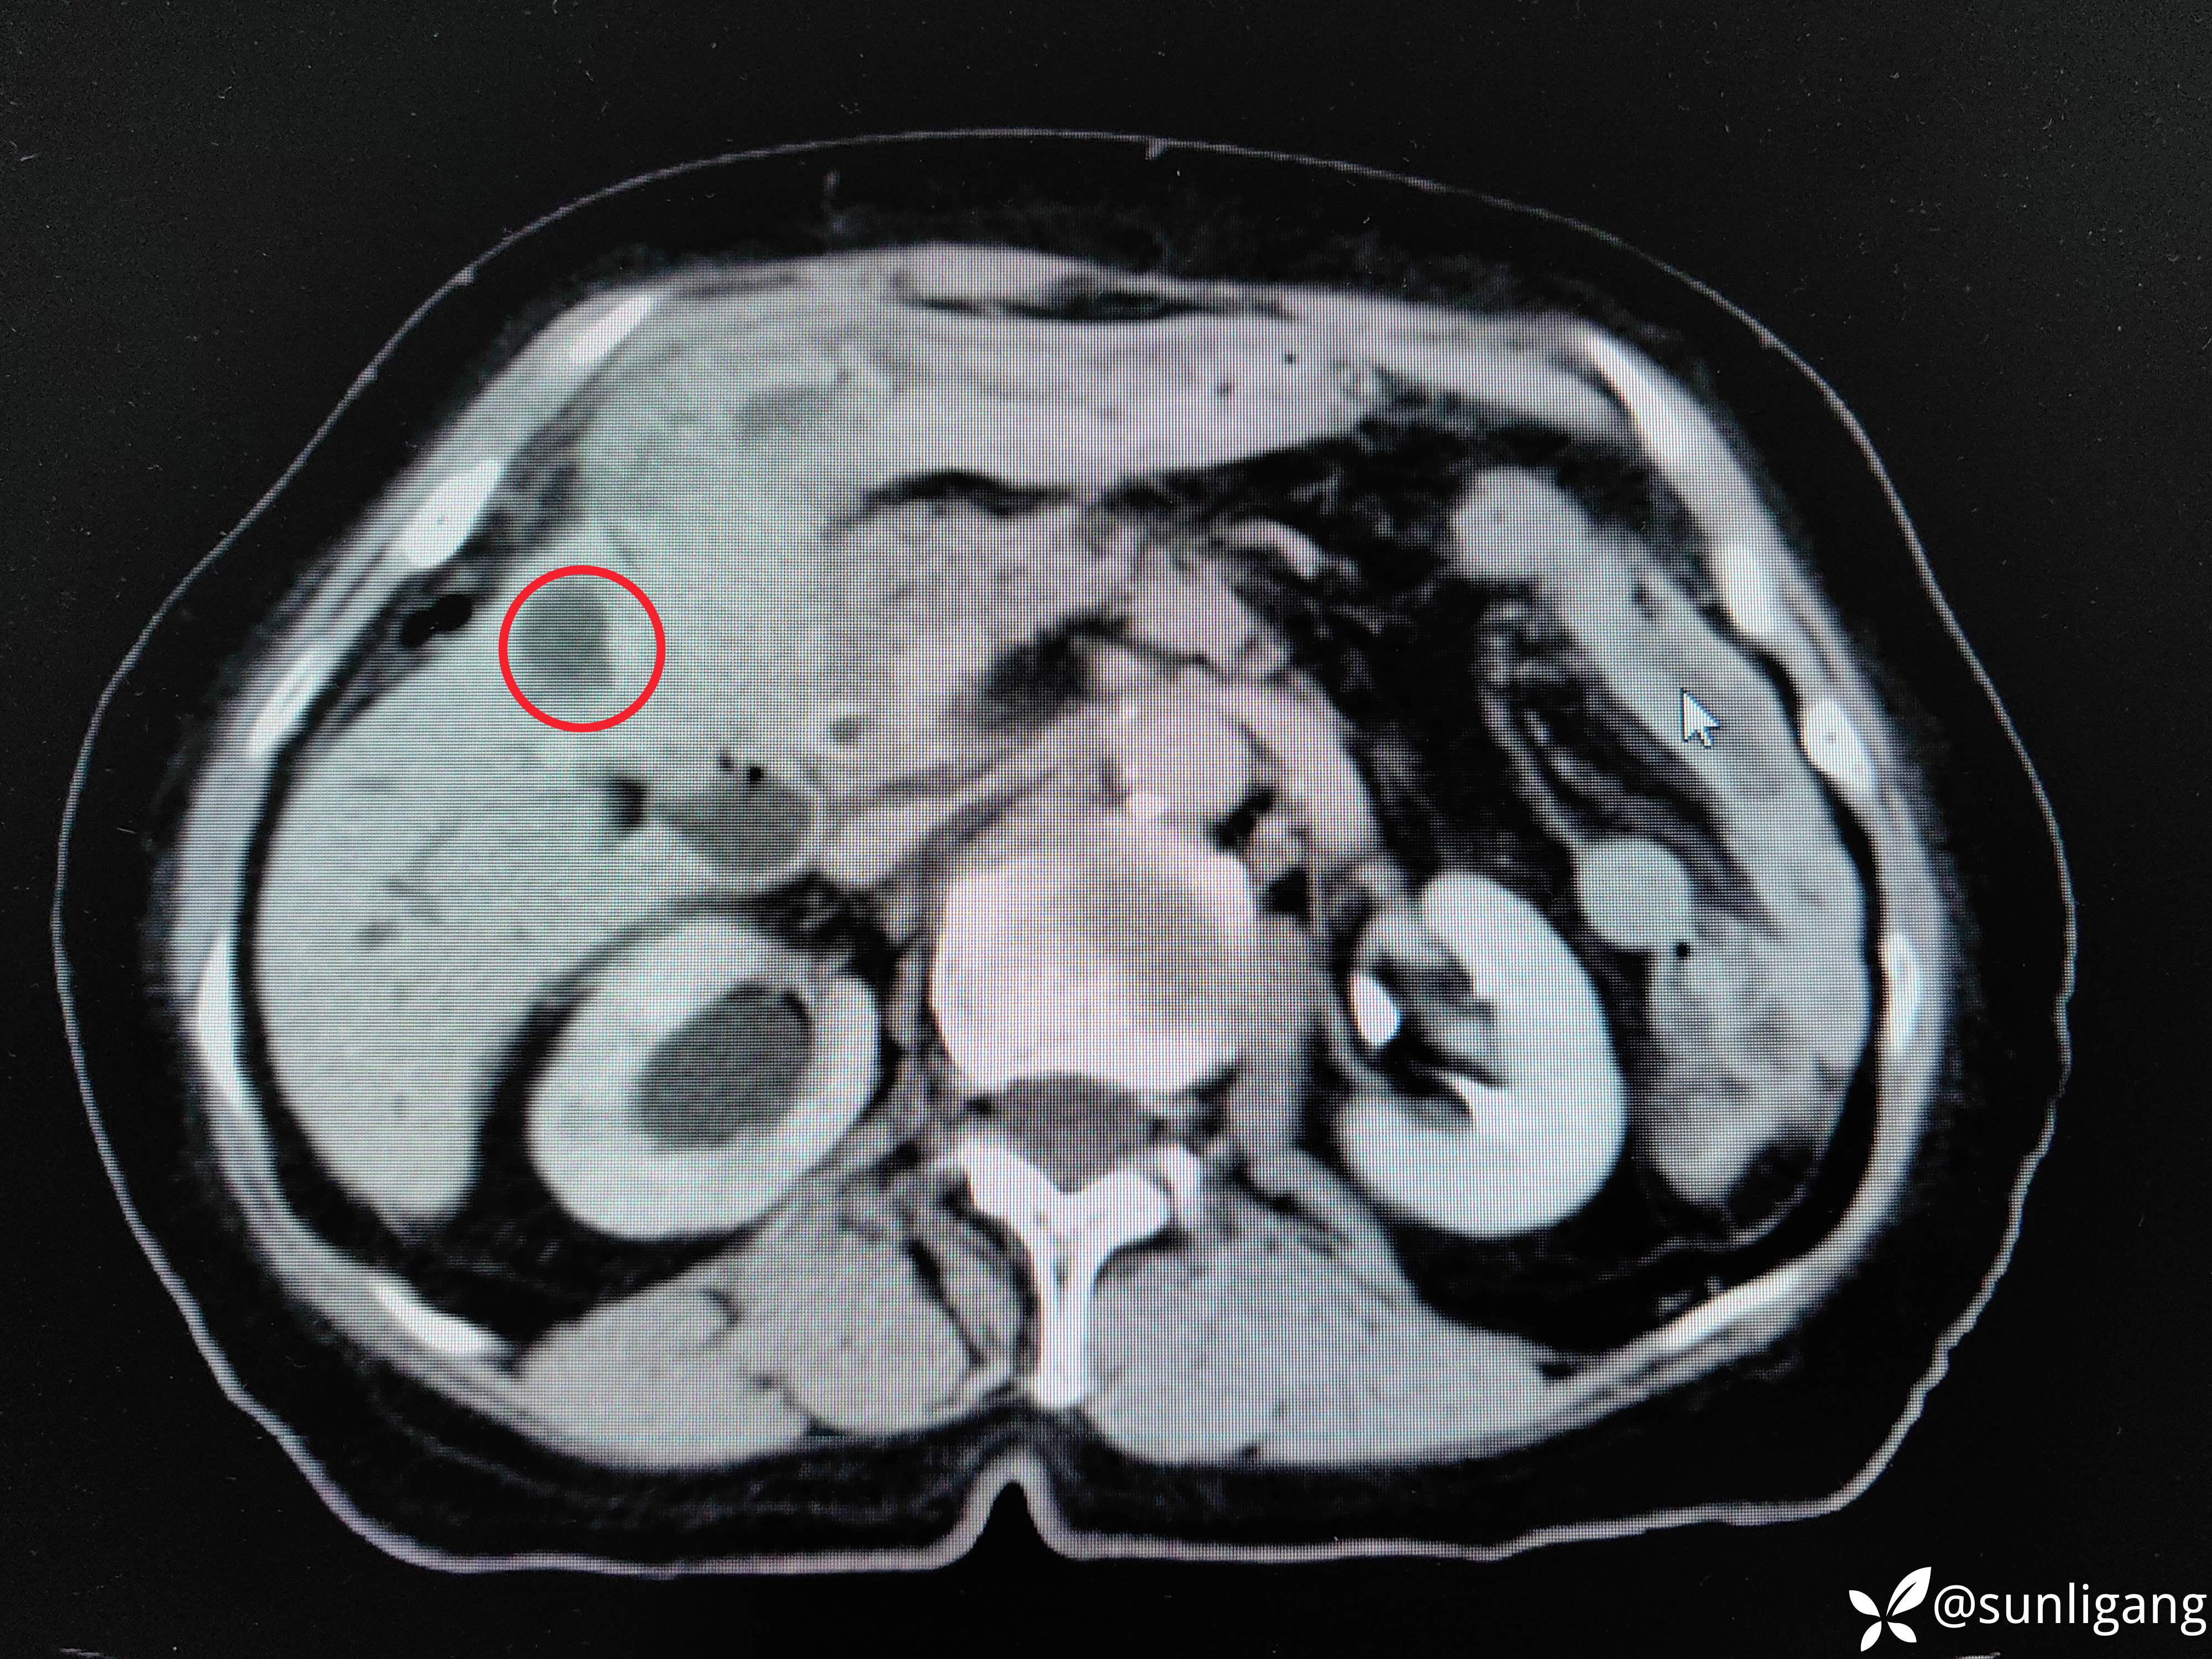

动脉期

增厚的胆囊壁及胆囊周围轻度强化的不均质组织、胆囊壁强化明显,还可见到右肝钙化点

延迟期(可见胃小弯侧胃壁增厚)

增厚的胃后壁,静脉期仍有明显强化